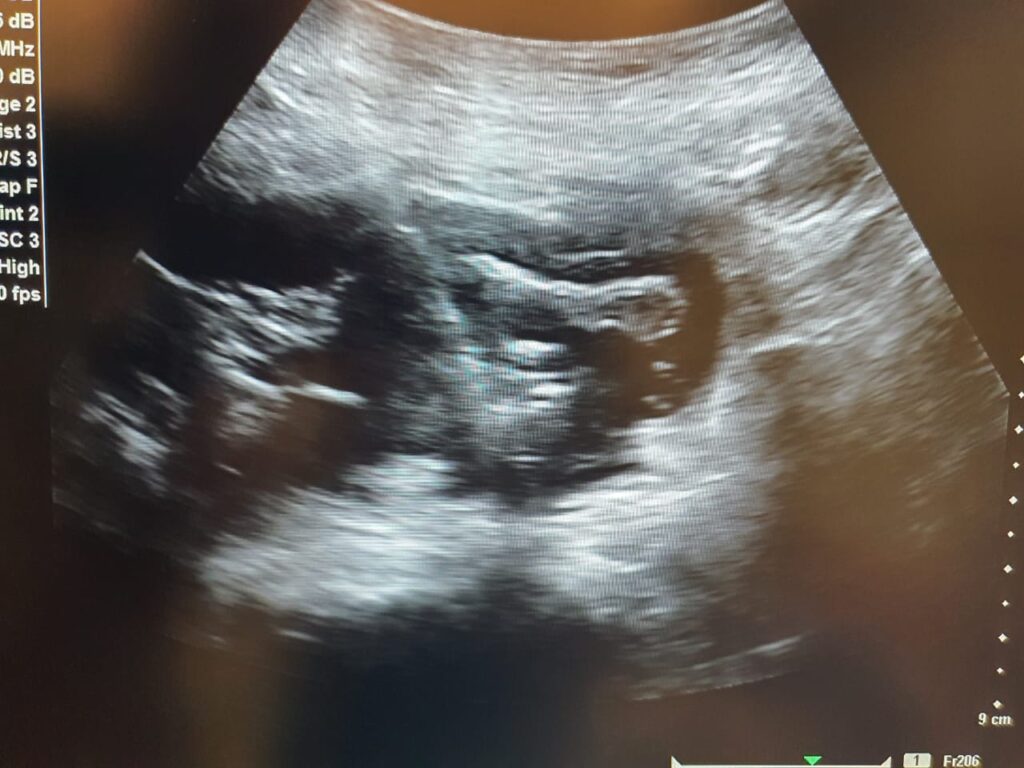

General Surgery NIRS Pakistan in Abbottabad offers cutting-edge diagnostic and intervention radiology services. Gall Bladder Fossa Abscess Drain Placement Expert infection drainage and abdominal care services available at NIRS. View More